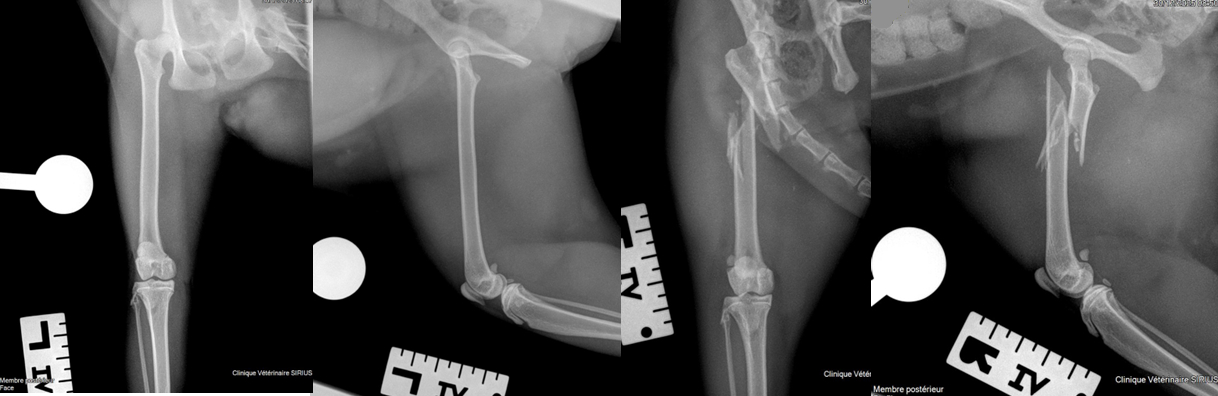

Radiographies orthopédiques d’un chat présentant une fracture fémorale

Deux incidences orthogonales ont été réalisées pour chaque membre, une vue de face et une vue de profil, afin de limiter les superpositions et fiabiliser l’interprétation.

Le positionnement est standardisé et reproductible, permettant une comparaison directe entre le côté atteint et le côté controlatéral.

Les clichés sont latéralisés gauche et droite, condition indispensable pour éviter toute ambiguïté d’identification.

La boule de calibration (diamètre 25 mm), placée à hauteur de l’os, permet d’effectuer des mesures précises directement sur les images.

La qualité d’image est compatible avec une lecture diagnostique, avec un contraste satisfaisant et une bonne netteté.

Cette méthodologie rigoureuse permet une planification chirurgicale très précise et reproductible.